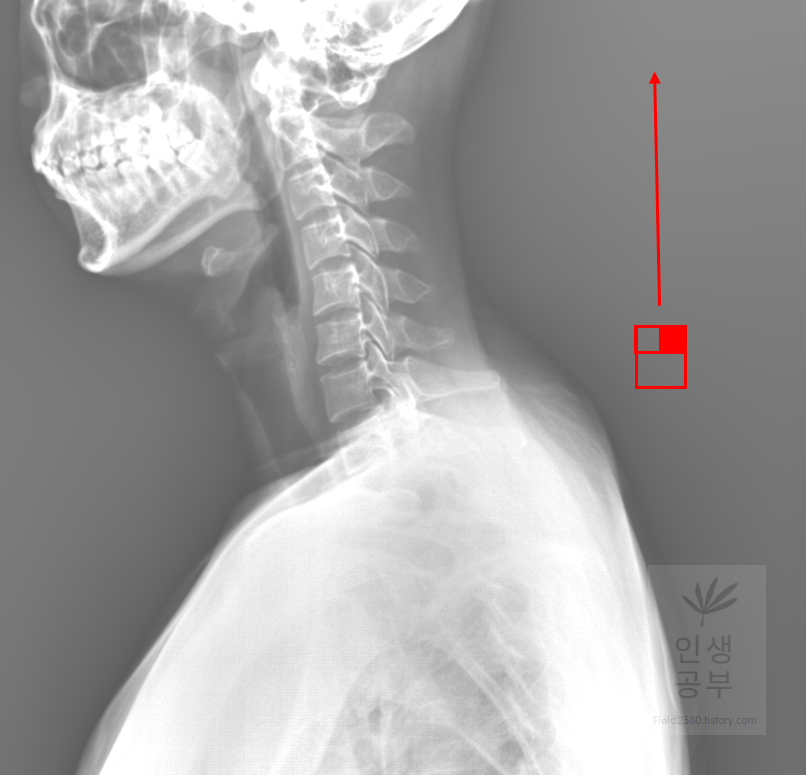

마우스 오른쪽 버튼을 누르고 위쪽 방향으로 드래그 해주면 화면이 밝아집니다.

마우스 오른쪽 버튼을 누르고 아래쪽 방향으로 드래그 해주면 화면이 어두워집니다. 두 버튼 모두 엑스레이가 잘 보이지 않을 때 적절하게 밝기를 조절하여 사용하시면 됩니다.

빨간색 네모칸으로 쳐진 대각선으로 그어진 줄 모양이 선을 긋거나 거리를 측정할 때 사용하는 버튼입니다.

선 긋기를 이용해서 Cobb각을 그린다고 가정했을 때 측정하려고 하는 곳을 처음에 누르고 드래그로 쭉 끌어다주면 위와 같은 선이 생기고 선의 길이가 자동으로 측정됩니다. 첫 번째 목뼈(C1) 선을 그리기 위해 제일 튀어나온 앞쪽 부분 가운데 지점에(Center of Anterior arch) 점을 찍어줍니다. 후궁(Posterior arch) 제일 좁은 부위 가운데 지점에 점을 찍어줍니다. 두 점을 연결해주는 선을 그어줍니다. 이 선 이름을 고리 뼈 선(APL : Atlas Plane Line)이라고 합니다. 점은 조금 더 정확하기 위해서 하는 것이 찍어도 되고, 점을 찍지 않은 상태에서 선을 그으셔도 무방합니다.

일곱번째 목뼈 추체 밑면(Inferior endplate of C7)과 평행한 선을 그어줍니다.